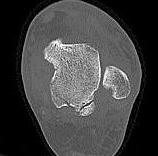

Posterolateral & Posteromedial tubercles

- separated by sulcus for FHL

- lateral larger than medial

PL tubercle

- size variable

- superior surface non articular, attaches PTFL

- inferior surface in continuity with posterior articular surface of talus

- an elongated lateral process (Steida lesion) can fracture

PM tubercle

- attachment of the deep & superficial deltoid ligaments